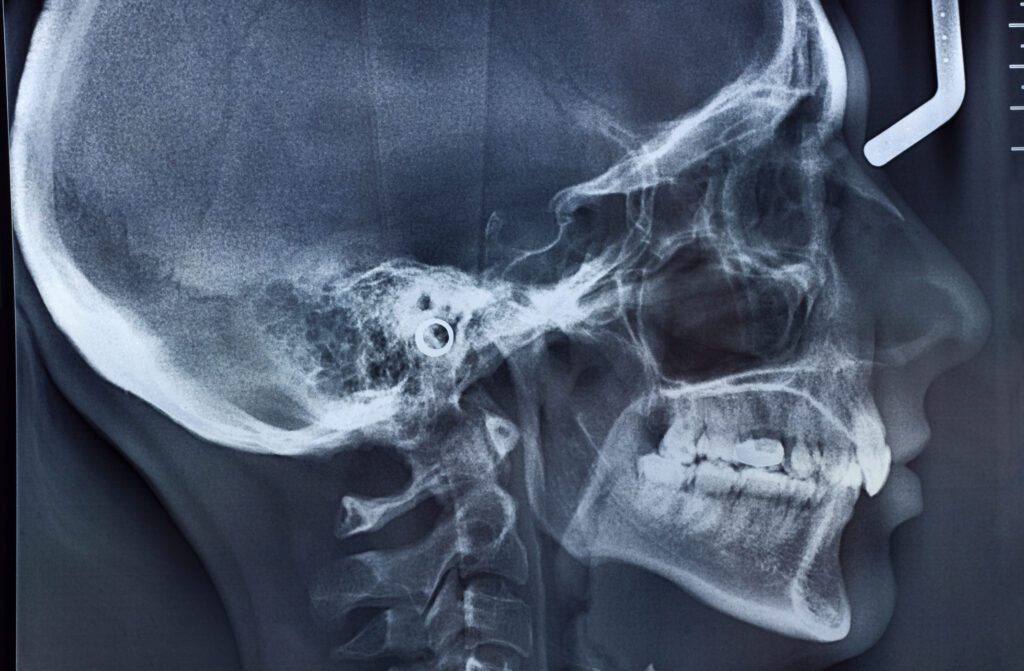

The joint that connects your jaw to your skull is the TMJ or temporomandibular joint. It is essentially the unsung hero behind your ability to chew, speak, and even express yourself. If your TMJ isn’t happy, you might experience jaw pain, clicking sounds, or even headaches. The dysfunction of your jaw joint is called temporomandibular joint disorder (TMD); however, most patients simply call this issue TMJ.

Our team uses advanced diagnostic tools and techniques to thoroughly analyze your bite. This involves assessing how your teeth meet when you close your mouth. As a result, we can identify any misalignments or irregularities.

We provide custom TMJ nightguards, also known as oral splints. Before treatment, we will take X-rays of your mouth to determine if this option is right for you.